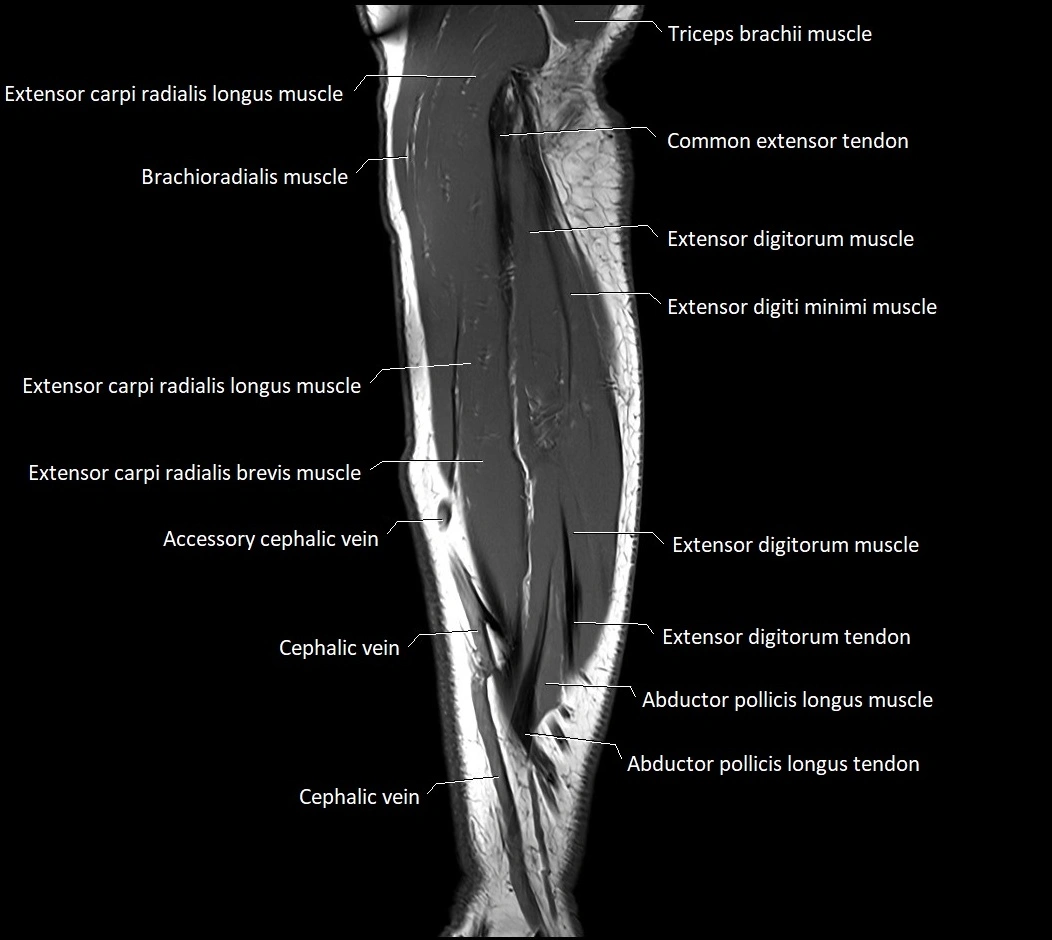

image

CT images